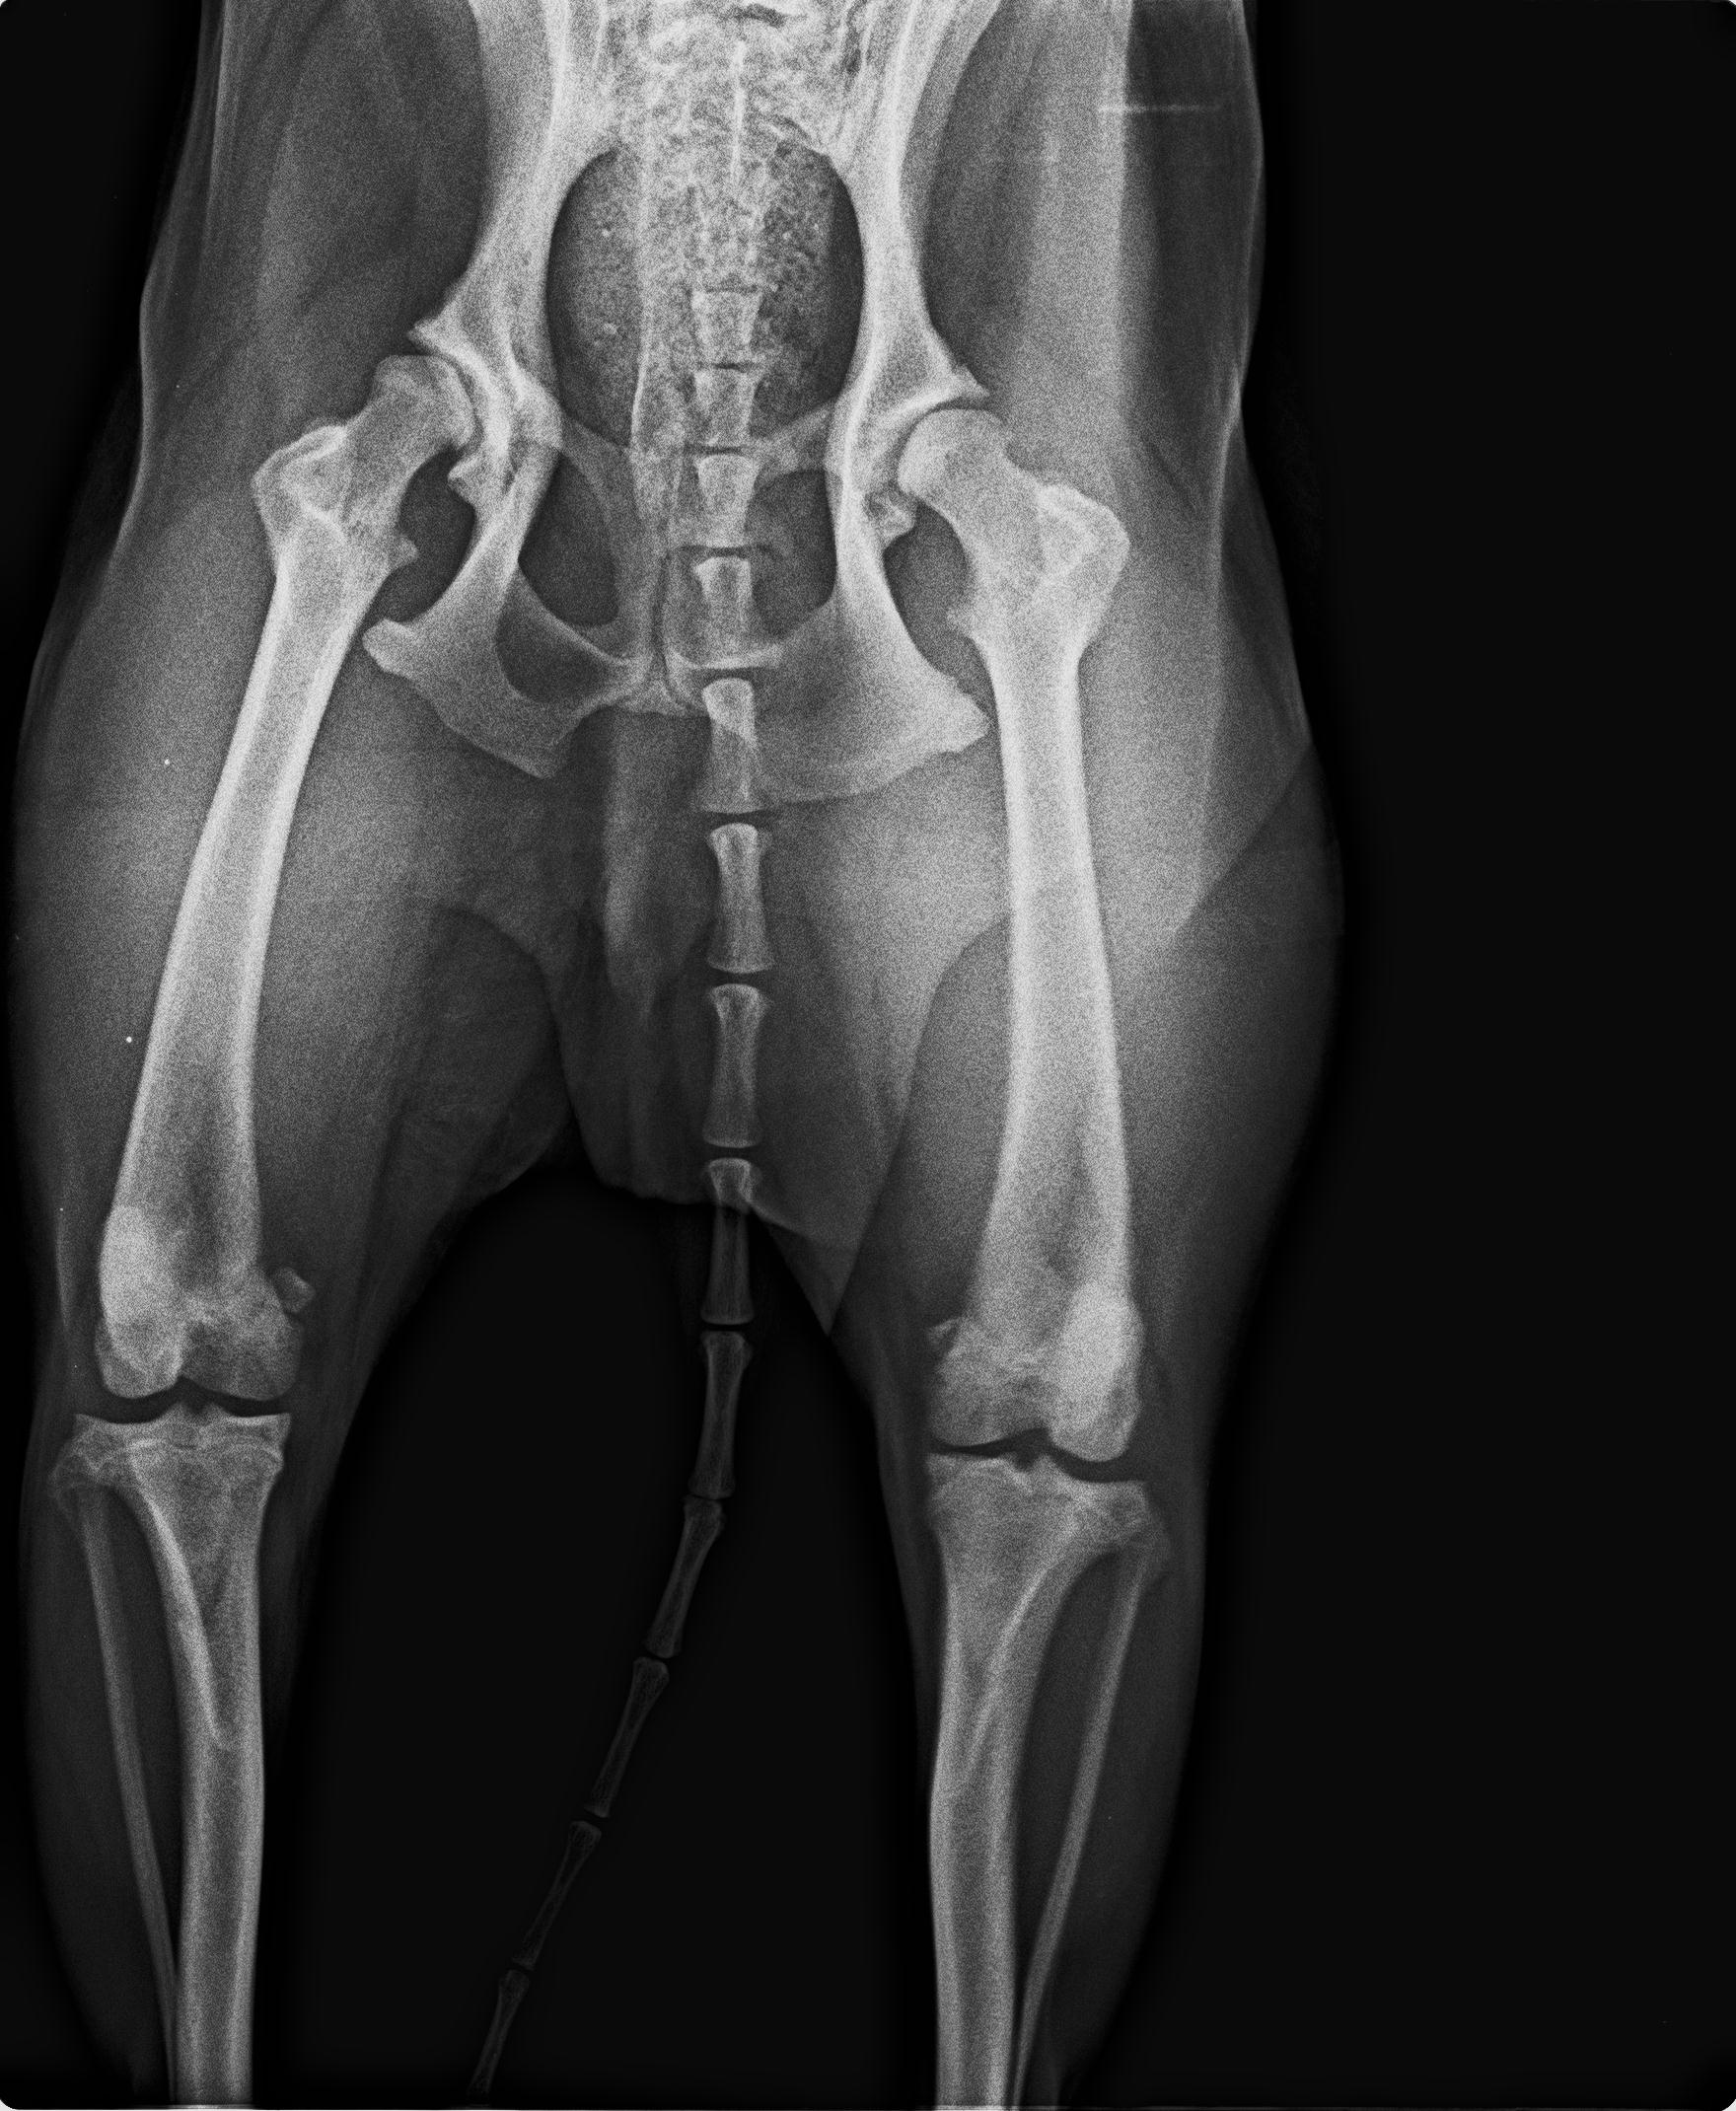

04.08.2025 neue Bilder, neues Video. Wir behandelten ihn mit Vitaminen und er schien sich gut zu entwickeln, er fing an, sich besser zu bewegen, obwohl wir mit der Zeit ein leichtes Hinken in seinem rechten Hinterbein bemerkten. Wir machten eine Röntgenaufnahme und der Tierarzt riet, den Oberschenkelkopf zu entfernen. Es dauerte viele Monate, bis er sich von der ersten Operation erholt hatte, so dass wir nicht wussten, ob wir auch das andere Bein operieren sollten. Aber dann begann Garfield, starke Schmerzen in seinem nicht operierten Bein zu haben. Wir gingen wieder zum Tierarzt und er wurde im Mai dieses Jahres an seinem zweiten Hinterbein operiert. Garfield ist ein Hund, der ein Zuhause mit einem großen Garten braucht, er ist kein Hund für Spaziergänge, da er sehr schnell müde wird. Vielleicht ist es eine Folge seiner Hinterbeinprobleme, als er ein Welpe war, deshalb sind seine Bedürfnisse anders als die anderer Hunde. Er wäre glücklich mit einem schönen, großen Garten, einer liebevollen und verständnisvollen Familie und viel Ruhe – mehr braucht Garfield nicht, um der glücklichste Hund der Welt zu sein.